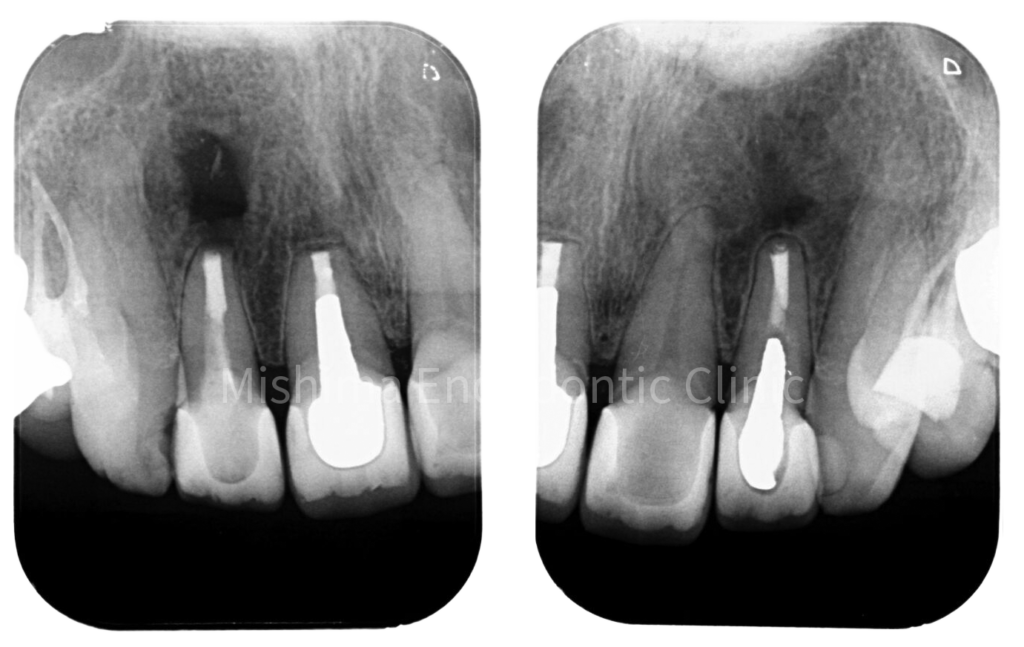

Before

術前